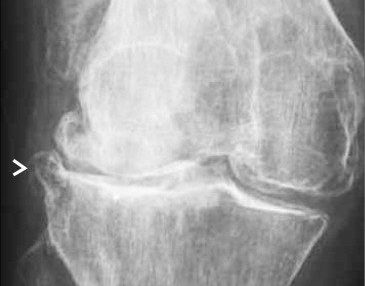

The management of chondral disease poses challenges due to its poor healing potential. Biomechanical and biological changes can accelerate degeneration, leading to end-stage osteoarthritis (OA).

The study, approved by the Ethics Committee, involved 30 patients with diffuse degenerative chondral lesions treated with autologous micro-fragmented adipose tissue between January and December 2014. Clinical evaluations were conducted at 3 years post-treatment.

Patients not requiring additional treatments maintained outcomes observed at 1 year, with significant improvements in functional scores including Tegner Lysholm Knee, VAS pain, IKDC subjective, and total KOOS.

The study demonstrates sustained benefits of autologous micro-fragmented adipose tissue in treating diffuse degenerative knee chondral lesions at mid-term follow-up, supporting its role as an adjunct in surgical procedures.